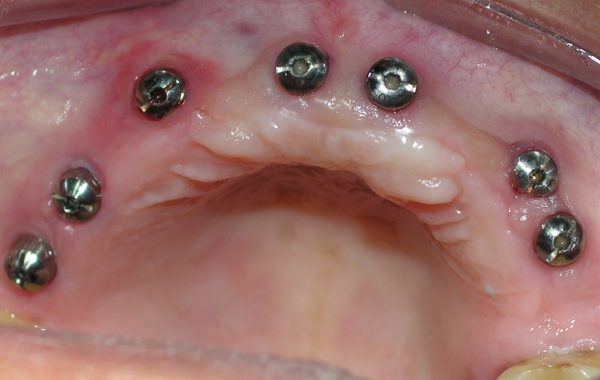

Paciente #5

La siguiente paciente es una Señora. de 65 años de edad, la cual no tenía dientes en el maxilar y utilizaba una dentadura total convencional, la cual cubre el paladar totalmente. La paciente quería otra opción protésica ya que el paladar de la dentadura le ocasionaba nauseas además de que perdía el sabor de los alimentos.

Se le colocaron siete implantes para realizarle una dentadura sin paladar, la cual es más delgada y el paladar queda libre.

caso 5-2

Se unieron estos implantes por medio de dos barras de oro, para soportar la dentadura y darle mayor retención.